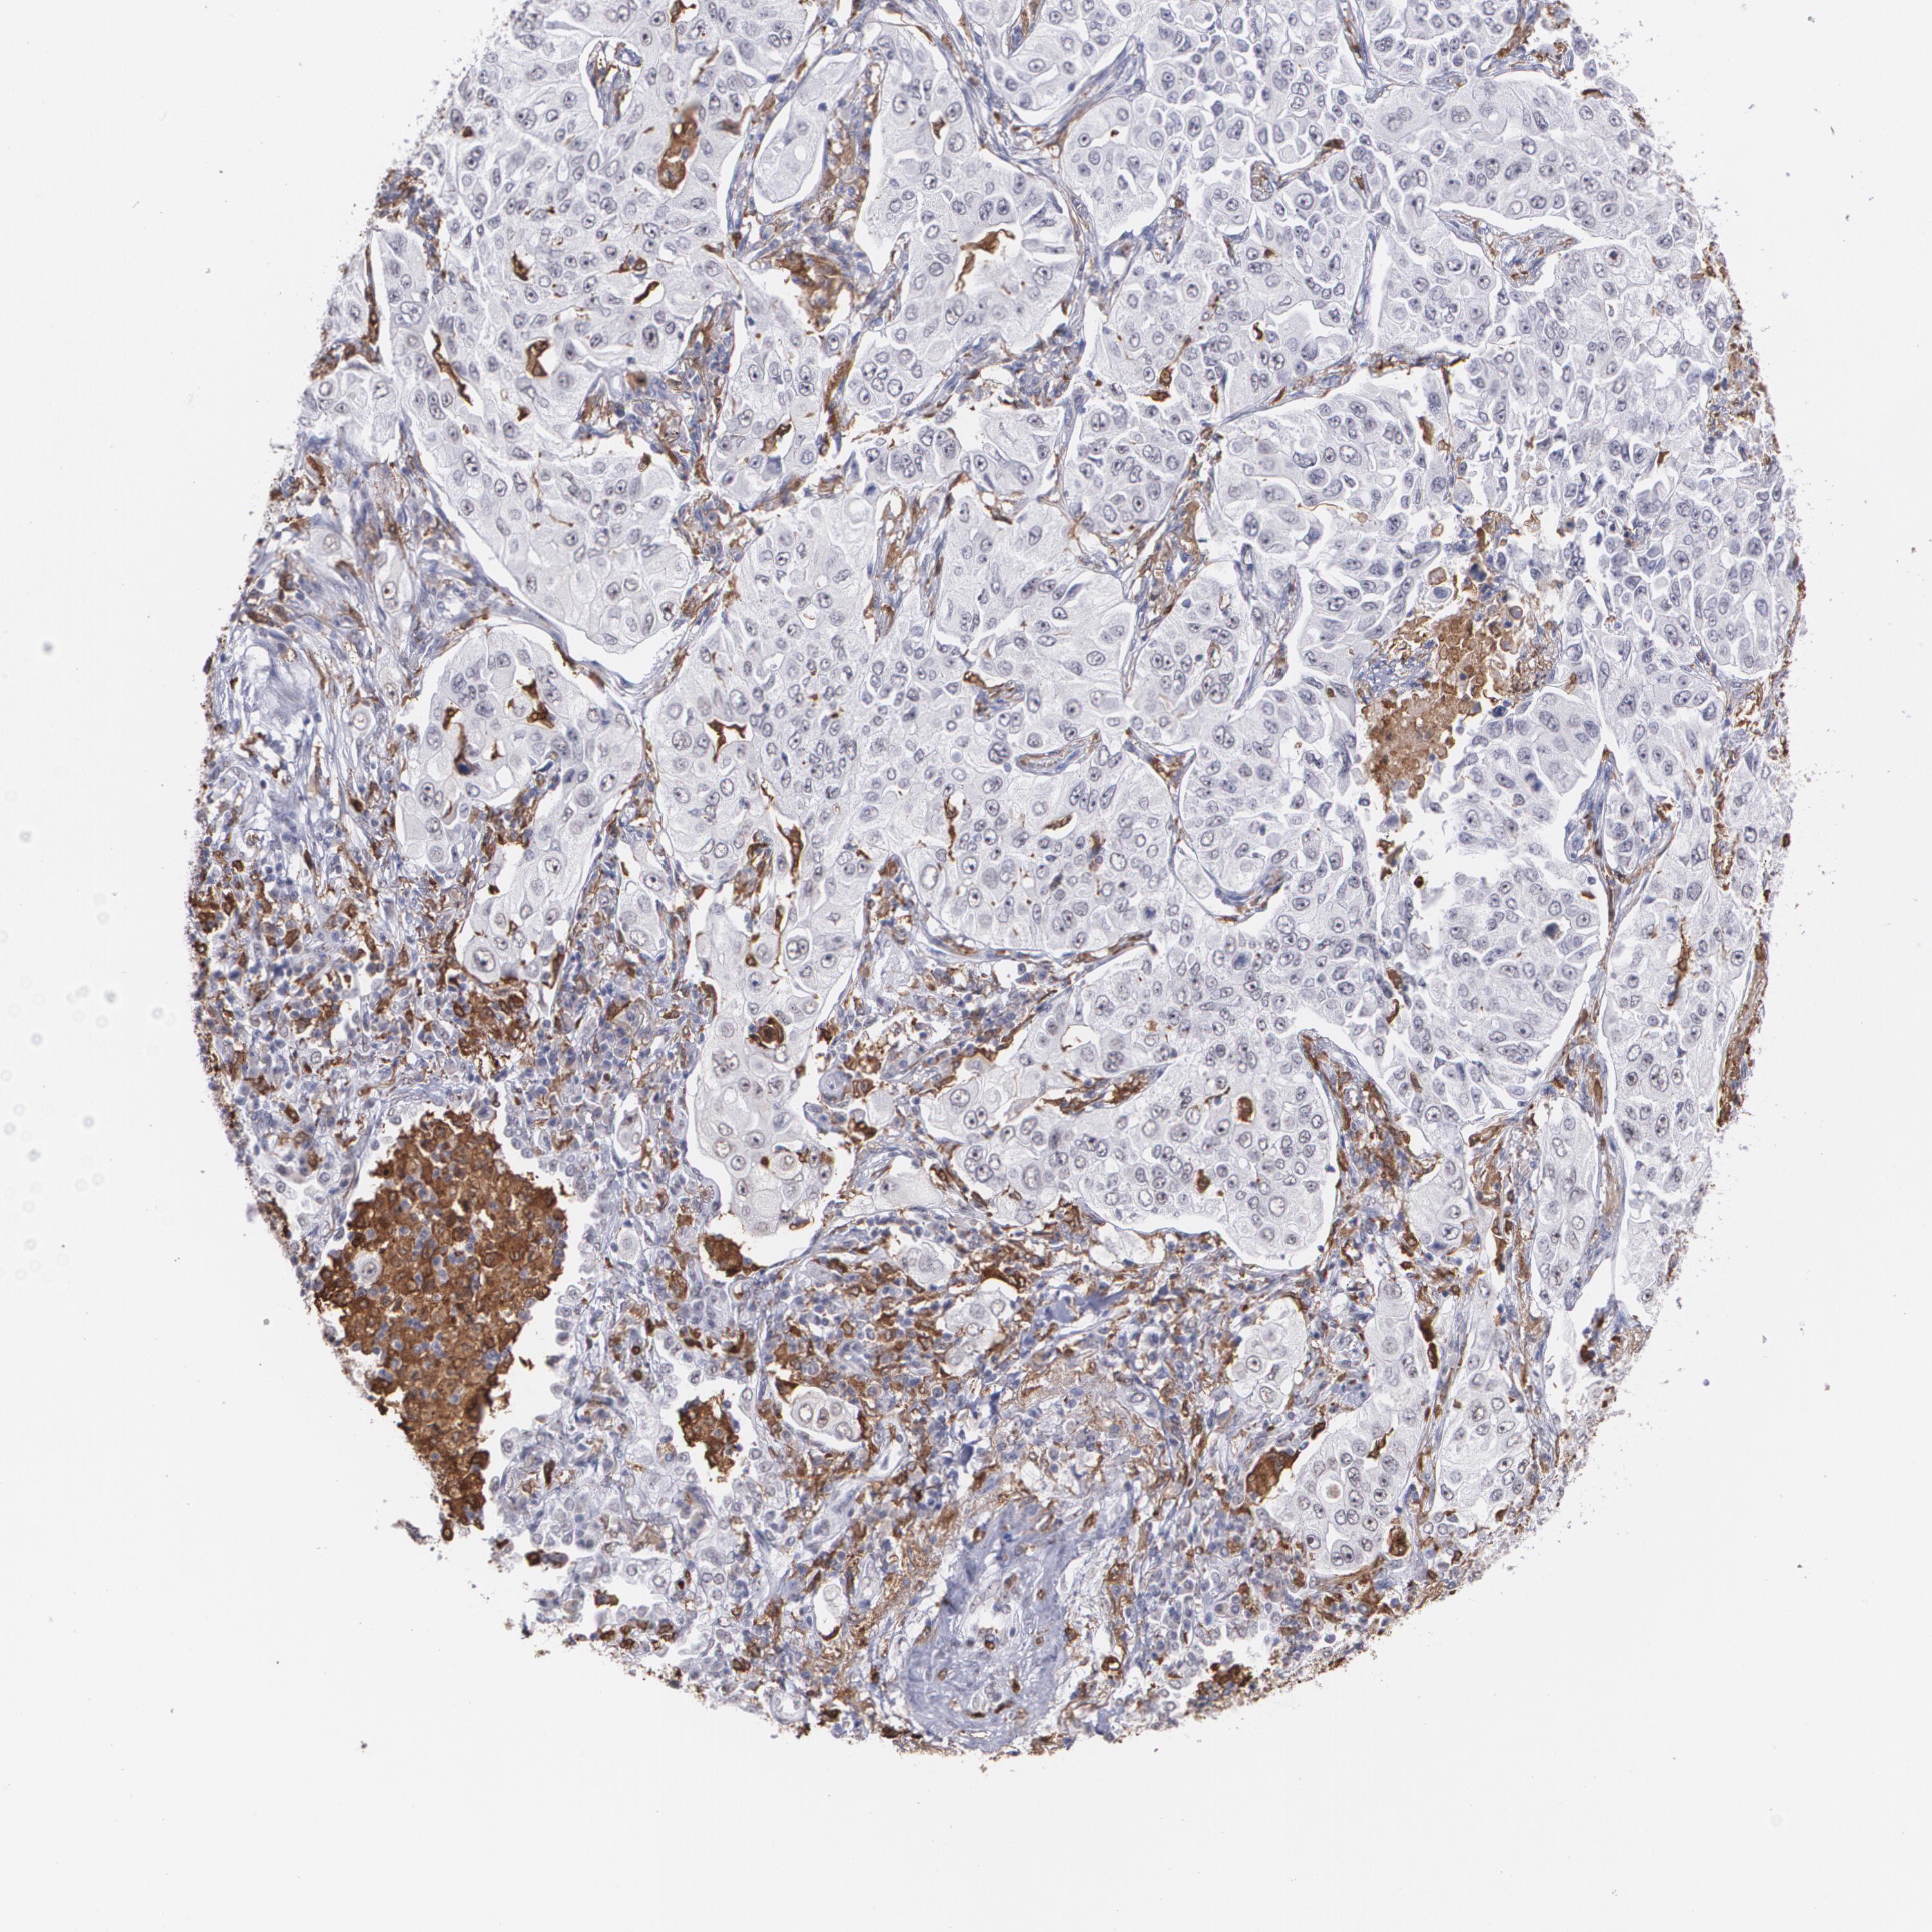

NCF2 is potential prognostic, high expression is unfavorable in Lung Adenocarcinoma (validation)

Best expression cut offi

Based on the FPKM value of each gene, patients were classified into two groups and association between prognosis (survival) and gene expression (FPKM) was examined. The best expression cut-off refers the FPKM value that yields maximal difference with regard to survival between the two groups at the lowest log-rank P-value. Best expression cut-off was selected based on survival analysis .

When clicking on this number, the vertical dashed line indicating cut-off, the interactive survival plot, and the Kaplan-Meier curve will be adjusted to show results based on the best expression cut-off.

: 39.67

Average pTPM 62.0

Number of samples 105